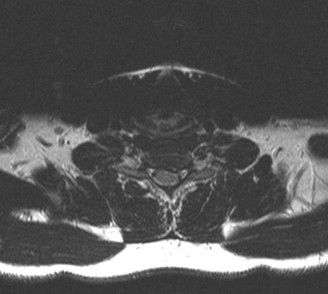

Prognosis of central cord syndrome? Indications for surgery for this disorder? CASE 2 A 56-year-old man presents to you with a chief complaint of severe right buttock, posterior thigh, and lower leg pain for 12 weeks. It radiates to the lateral aspect of his foot, and it is worse with sitting or standing for prolonged periods and with walking. Now over the past 2 weeks, he reports difficulty with toe push-off on the right side. Treatment so far has been nonsteroidal anti-inflammatory drugs (NSAID), physical therapy, and an epidural injection without significant relief. Physical examination findings include 4/5 right ankle plantar flexion, a positive straight leg raise on the right, and an absent right Achilles tendon reflex. Images of his lumbar spine are shown in Figures 1–4 and 1–5.

The correct answer is (C). The patient presents with classic right S1 radiculopathy and new onset plantar flexion weakness. The images demonstrate a right-sided paracentral disc herniation at L5/S1 compressing the traversing S1 nerve root. Despite nonoperative management, he continues to have severe pain and new weakness. Continued physical therapy or an epidural injection is unlikely to improve the patient’s pain at this time. In the setting of neurological decline, surgery is more strongly indicated. Lumbar discectomy is the most appropriate procedure for this patient. Fusion would only be indicated if there were radiographic signs of instability, which are not present.